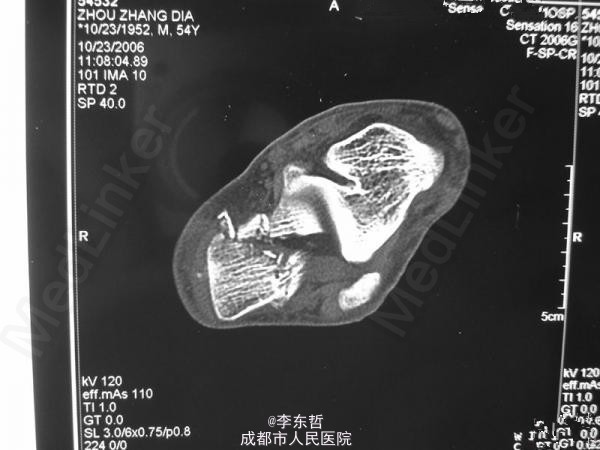

左足跟骨骨折

跟骨骨折

患者男性,60岁;高处坠落致左跟部肿痛10天入院,查体示左跟部略肿,压痛,无皮裂出血;予刚针撬拨术复位。